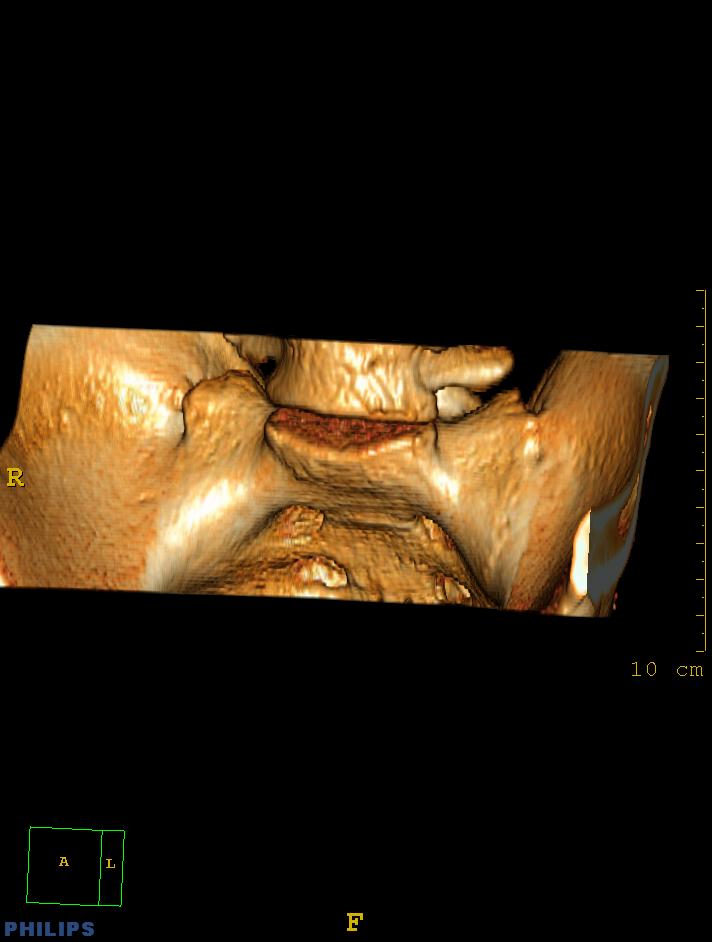

标题: CT14032:M34Y,双侧骶髂关节 [打印本页]

标题: CT14032:M34Y,双侧骶髂关节

m,34岁,腰痛三年,腰椎活动度明显减低,x片示腰椎竹节样改变

双侧骶髂关节骨性融合,软骨下囊性变,结合脊柱竹节样改变,典型的强直性脊柱炎。